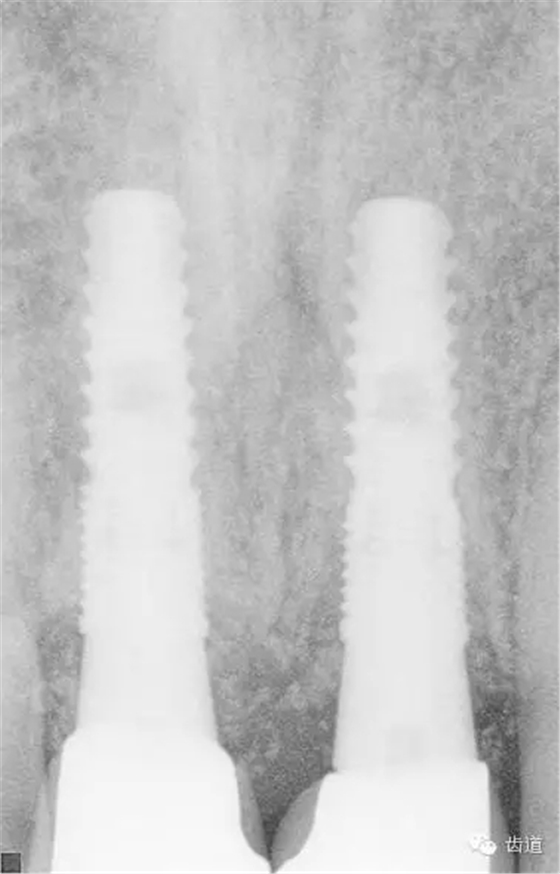

放射檢查:11,21根中三分之一至根尖三分之一處折斷。

術(shù)前放射片

戴牙后CT